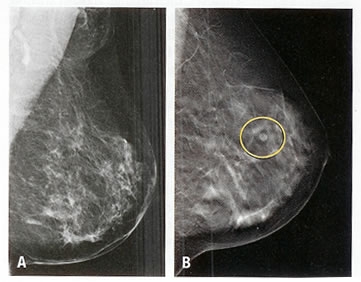

در یک تحقیق گسترده که برروی 105986 زن بالای 28 سال انجام شد.

نشان داده است که مصرف الکل حتی در مقادیر کم هم خطر سرطان پستان نوع تهاجمی را افزایش میدهد.

براساس این مطالعه که نتایج آن در مجلة داخلی آمریکا منتشر شده است مصرف 12-6 لیوان الکل در هفته خطر سرطان سینه را 22 درصد افزایش میدهد.

و اگر این مصرف به 30 لیوان در روز برسد خطر بروز سرطان سینه 51 درصد افزایش مییابد.